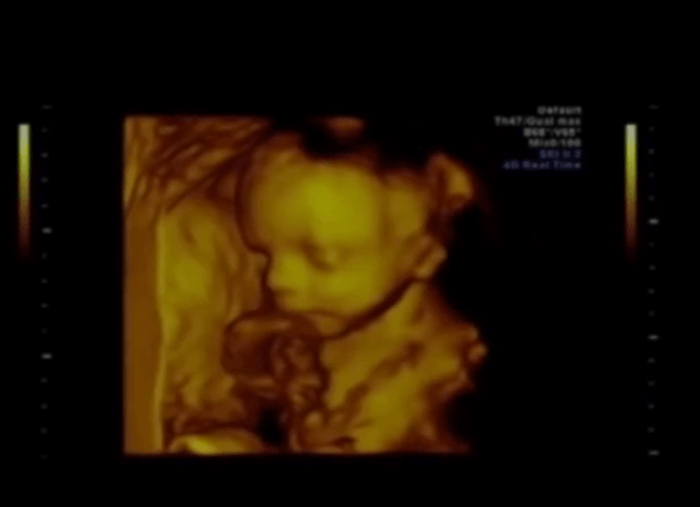

This Is a Baby